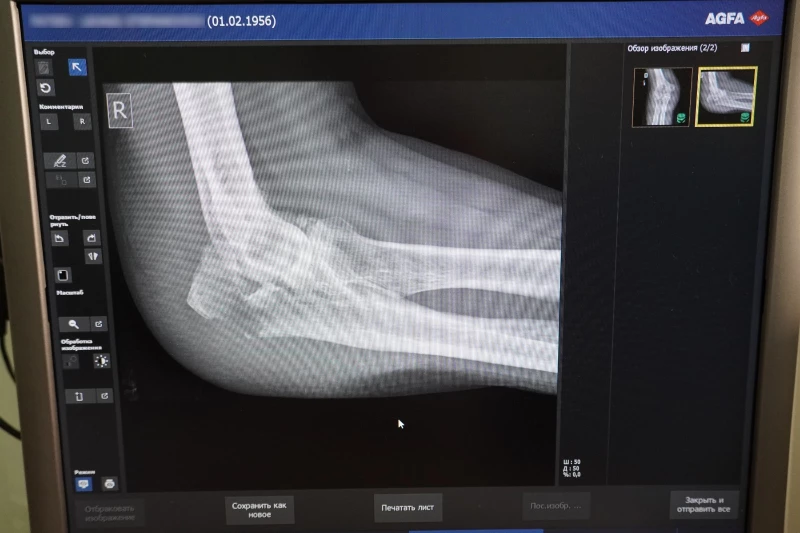

Самые уязвимые части тела в период гололедицы — это нижние и верхние конечности, говорит Константин Карапыш. Первыми под удар попадают нижняя треть предплечья и лодыжки — область голеностопного сустава.

Это связано с тем, что, поскользнувшись, человек рефлекторно выставляет руку вперед и падает на нее всем своим весом. Отсюда самая распространенная травма — перелом дистального метаэпифиза лучевой кости.

Лодыжку же человек повреждает, поскользнувшись на каком-нибудь бугристом месте. Нога подворачивается внутрь или наружу — связки испытывают сверхнатяжение, из-за чего кость буквально лопается.

За зиму врачи-травматологи сталкиваются с самыми разными травмами, полученными из-за гололедицы — чаще всего это ушибы, растяжения, вывихи крупных и мелких суставов, а также переломы. Врач подчеркнул, что не специалисту отличить одно от другого совсем непросто. Поврежденная конечность одинаково отекает, появляются гематома и болезненность. Из-за этого люди могут не обращаться к врачу несколько дней, надеясь, что все пройдет само.

«Так делать точно не стоит. Если вы получили травму, то стоит как можно скорее обратиться в травмпункт. Там сделают рентген-снимок, и после этого врач точно скажет, ушиб это или серьезный перелом, а после назначит лечение», — предупреждает травматолог.

От вида и степени травмы будет зависеть лечение и время восстановления. Так, поврежденная лодыжка без смещения будет заживать шесть недель. А при оскольчатом переломе человеку может потребоваться оперативное вмешательство и долгая реабилитация.